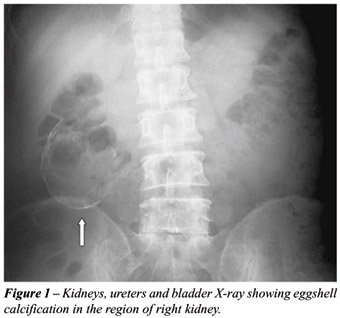

A thirty-year-old man was investigated for abdominal pain and a palpable mass in the right lumbar region. He had no associated urinary symptoms or bowel dysfunction. The only significant history was a pulmonary tuberculosis ten years before for which he was adequately treated. He had no history of any operative intervention or trauma in the past. On physical examination, he was normotensive and had a 7cm hard, nontender bimanually palpable lump with restricted mobility in the right lumbar and umbilical region. No bruit was present over the lump. An investigation revealed a normal urine routine and microscopic examination, sterile urine culture and a normal hemogram. Serum creatinine, blood urea nitrogen and serum calcium were unremarkable. Urine for acid-fast bacillus microscopy was negative thrice and urine polymerase chain reaction for Mycobacterium tuberculosis was also negative. Indirect hemagglutination test for hydatid was negative. KUB film revealed an eggshell like calcification in the right kidney region (Figure-1). Subsequent ultrasound and computerized tomography showed a well defined, cystic right kidney (Figure-2). Renal scan confirmed the absence of any functional renal parenchyma on the right side. On cystoscopy, the right orifice was normal and no urine flow was detected. Right retrograde pyelogram revealed a thin ureter, which was obstructed at the ureteropelvic junction. Laparoscopic nephrectomy was done. Multiple sections examined showed a fibrocollagenous cystic wall with hyalinization, calcification and ossification. Certain areas with intact epithelial lining and thyroidization of renal tubules were also observed. No granulomatous inflammation or parasite was present.